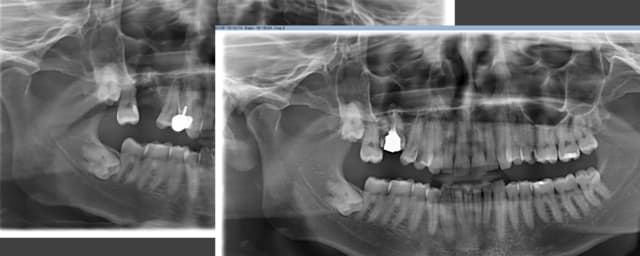

Je me permet de remonter le fil car j'en ai fait une belle; j'ai réussi à enlever les racines mesio vest et disto vest de cette 16, mais en fesant une belle communication.

Je suis resté zen, mais n'est pas osé aller chercher la palatine, de peur de l'envoyer dans le sinus.

J'ai mis des éponges et fais un point en croix pour refermer et l'ai prévenu, plus amox solupred sterimar lamaline.

Que faire à court terme, il part dans 2 mois vivre en chine ...

Pano kzict8 - Eugenol